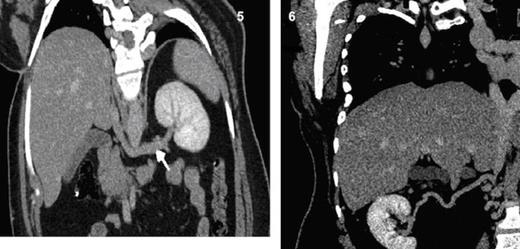

Coronal MPR CT image shows a long left renal vein seen draining into the intra-hepatic segment of IVC. Fig. 6 Coronal MPR CT image shows a right renal collateral vessel draining into hypoplastic segment of IVC.

The right renal vein is absent represented by long tortuous collateral draining into hypoplastic segment of IVC (Fig. 6) and multiple collaterals draining into the retroperitoneal venous plexus (Fig. 7). The right great saphenous vein exhibits drainage into the distal part of right common femoral vein (Fig. 8).